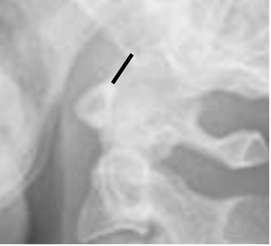

Para evaluar la alineación de la unión cráneo espinal, se mide la distancia entre el basión (Parte mas anterior del agujero occipital) y el borde superior de la odontoides y no debe ser mayor de 12 mm. (38). (Fig 188).

Fig 188. Alineación de la unión craneoespinal.

Rx lateral. Distancia entre el basion y la punta de la odontoides, menor de 12 mm.